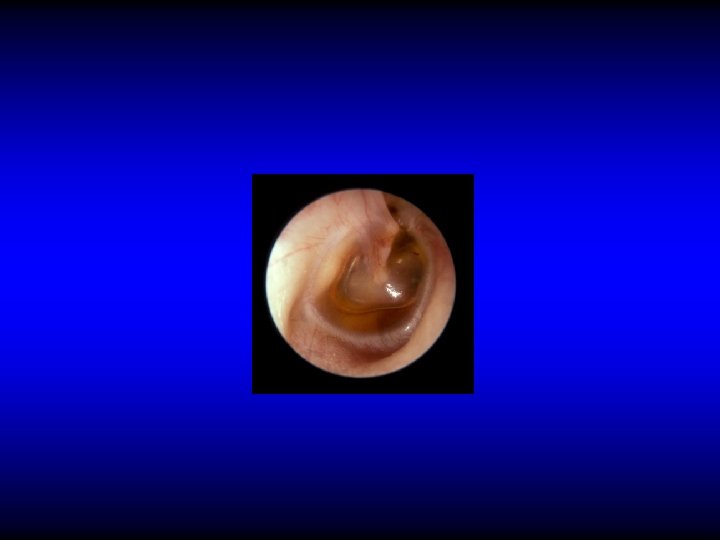

Otoscopic examination • Discharge – Present in TT type if active but may be absent – Usually is present in AA type • Perforation – Central: in TT type – Marginal or attic in AA type with cholesteatoma

Perforation in AA CSOM

Otoscopic examination • Discharge – Present in TT type if active but may be absent – Usually is present in AA type • Perforation – Central: in TT type – Marginal or attic in AA type with cholesteatoma • Polyps, granulation tissue, tympanosclerosis